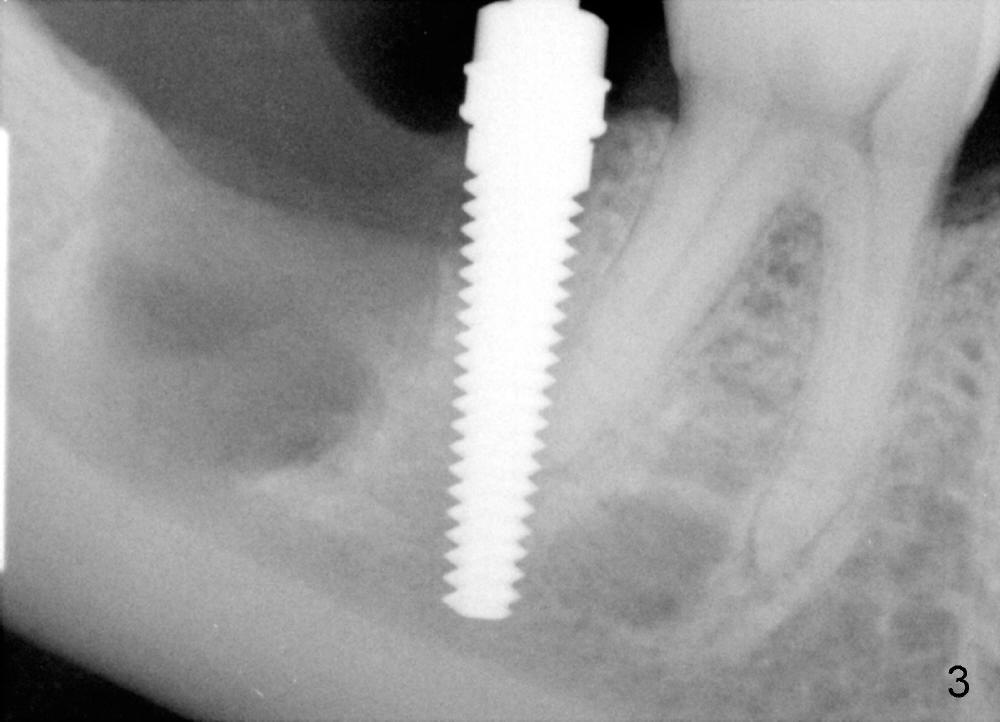

A: after obtaining verbal and written sx consent, Mepivacaine 54 mg, Xylo 34 mg, Septo 68, Epi 34 mcg infiltration, separated gingiva with periotome, pt had pain, Marcaine 9 mg, Xylo 34 mg, Epi 26 mcg infiltration and intraligamental injection, routine ext with forceps, curettage with serrated curette, lot of granulation tissue, until the bottom of the socket, close to presumptive inferior alveolar canal, tissue apparently running mesiodistally, easily removed without active hemorrhage, distal root has abundant calculus, distal socket apparently too large for implantation, copious irrigation, placed Clindamycin gauze x3, mesial socket flat (B-L width is much bigger than M-L one), inserted D1,2 spreader and D2 socket formers with difficulty, handles contact #30 distal crown, inserted RT 2,3,4 and tapered osteotomes 5x18 and 6x18 mm, trying to move the septum distally with much help, inserted 4.5x20 mm tap at 17 mm depth, stable, PA taken: tap close to #30 distal root, approaching IAN (Fig.3), changed to 5x17 tap at 14 mm without stability, when 6x17 tam is inserted at 14 mm, it is stable, PA taken: tap very close to #30 distal root (Fig.4), removed the tap (mesial wall of the mesial socket: no obvious perforation with distal root of #30) and droppd it  into in the distal socket, PA: tap tip overlaps IAN canal (Fig.5), discussed possible nerve injury and touching neighboring root, pt agreed to abort implant placement and place bone graft. placed collagen plug (CollaForm-Plug, Absorbable Collagen Wound DRef CFP1020_5, Lot CFP1020_1301)) in the bottom of the socket (to make room for nerve regeneration), inserted ~.6 cc CANCELL Oss (Mineralized Cancellous Human Allograft, distributed by Implandent LTD, .850-1 mm, 03-0494763/03-0494749, Product Code 06412201, mixed with .3 mg Osteogen (300-400 micron, Osteoconductive Synthetic Bioactive Resorbable Graft, Impladent LTD) into sockets, placed another collagen plug on the top of bone graft, 4-0 chromic gut suture (figure 8 and 1 interrupted), perio dressing, hemostatic. Pt was doing well. POI (oral) and extra gauze given. Continue Amoxicillin, Chlorhexidine, Medrol and Norco, Vitamin B complex recommended